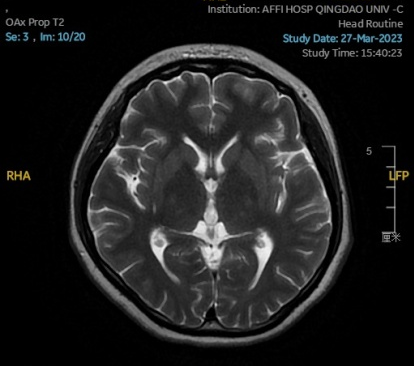

2023.01.18颅脑MR平扫示双侧基底节区及桥脑异常信号,考虑渗透性神经脱髓鞘综合征可能,见图1。

图1 2023.1.18颅脑MR成像示双侧基底节区及桥脑见对称性片样长T1长T2信号,FLAIR呈高信号。脑室、脑池、脑沟、脑裂未见明显异常。中线结构居中。小脑、脑干未见明显异常信号。